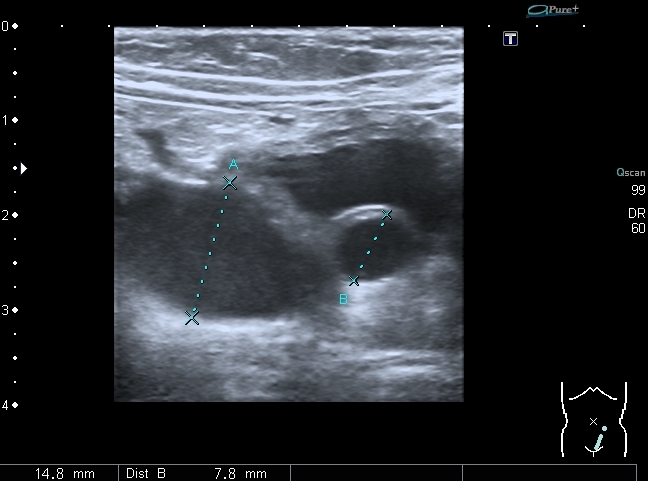

При УЗИ: правая почка - не изменена, в левой - незначительное расширение ЧЛС

В нижней чашечке левой почки - конкремент до 5 мм

Конкремент даёт твитлинг - артефакт

В мочевом пузыре определяется достаточно большое уретероцеле слева, периодически увеличивающееся и пульсационное уретероцеле справа. Левый мочеточник в нижней трети резко расширен.